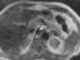

Aneurysm of abdominal aorta or its branches

The abdominal aorta is the largest artery in the abdominal cavity. As part of the aorta, it is a direct continuation of the descending aorta (of the thorax). [Source: Wikipedia ]